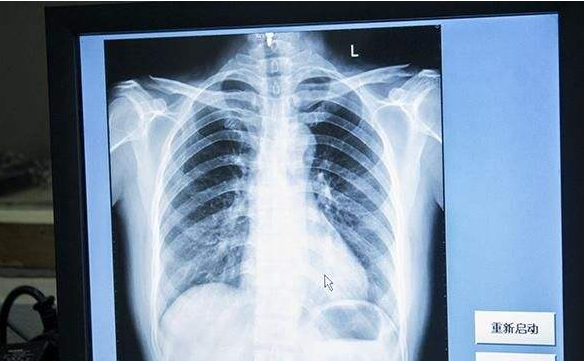

麻烦帮看下这个dr胸片,疑似百草枯中毒,从胸片上来看患者预后如何?

被送来做胸片,十几年前ct还不是首选,做的胸透

术后胸片

求结果一张基层医院的全胸片